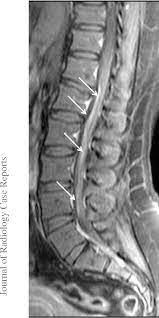

However, it can reveal nerve root enhancement and may be an effective diagnostic adjunct. The severity on mri does not correlate with severity of the clinical condition. Fisher syndrome, a clinical variant of guillain­ barre syndrome characterized by ataxia, are­ flexia, and ophthalmoplegia, brain stem lesions have been described with cranial mr.imaging (8). Its signs and symptoms are similar to those of other neurological disorders and may vary from person to person. Sagittal and axial post contrast t1 fs images shows smooth thickening and abnormal enhancement of the cauda equina and the ventral nerve roots. Moreover, gbs is also associated with any vaccination. Your doctor may then recommend: It is characterized by a triad of ophthalmoplegia, ataxia, and areflexia.

Clinical presentation is usually characterized by rapidly progressive, ascending, and symmetric paralysis of the extremities. Although no abnormalities were observed on brain and spinal magnetic resonance imaging and electroencephalography, peripheral nerve conduction velocity tests failed to evoke motor and sensory nerve action potentials. It is characterized by a triad of ophthalmoplegia, ataxia, and areflexia. Sagittal and axial post contrast t1 fs images shows smooth thickening and abnormal enhancement of the cauda equina and the ventral nerve roots. Scott olson / staff / getty images Moreover, gbs is also associated with any vaccination. Your doctor may then recommend: Mri is sensitive, but nonspecific, for diagnosis. The study findings are published in the journal neurological research. Mr imaging findings in eight patients (three male, five female; Immune checkpoint inhibitors (icis) have been increasingly used in the treatment of various types of tumors with favorable results. The most common result is a weakness and numbness that starts at the tips of the fingers and toes and spreads inward toward the body. Guillain barré syndrome (gbs) is characterized by demyelination and axonal degeneration of peripheral nerves.

Its signs and symptoms are similar to those of other neurological disorders and may vary from person to person. Sagittal and axial post contrast t1 fs images shows smooth thickening and abnormal enhancement of the cauda equina and the ventral nerve roots. Mri is sensitive, but nonspecific, for diagnosis. The diagnosis is usually established on the basis of symptoms and signs, aided by cerebrospinal fluid findings and electrophysiologic criteria. Clinical presentation is usually characterized by rapidly progressive, ascending, and symmetric paralysis of the extremities. Scott olson / staff / getty images Your doctor is likely to start with a medical history and thorough physical examination. It is the most common cause of rapidly progressive flaccid paralysis.

On csf analysis, the cell count is normal in 85% of patients, and high protein values are seen in 64%. Sagittal and axial post contrast t1 fs images shows smooth thickening and abnormal enhancement of the cauda equina and the ventral nerve roots. Clinical presentation is usually characterized by rapidly progressive, ascending, and symmetric paralysis of the extremities. Fisher syndrome, a clinical variant of guillain­ barre syndrome characterized by ataxia, are­ flexia, and ophthalmoplegia, brain stem lesions have been described with cranial mr.imaging (8). Typically, both sides of the body are involved, and the initial symptoms are changes in sensation or pain often in the back along with muscle weakness, beginning in the feet and hands, often spreading to the arms and upper body. Mr imaging findings in eight patients (three male, five female; With treatment, people may improve more quickly. However, it can reveal nerve root enhancement and may be an effective diagnostic adjunct. Your doctor may then recommend: The most common result is a weakness and numbness that starts at the tips of the fingers and toes and spreads inward toward the body. Moreover, gbs is also associated with any vaccination. Mri is sensitive, but nonspecific, for diagnosis. Immune checkpoint inhibitors (icis) have been increasingly used in the treatment of various types of tumors with favorable results.